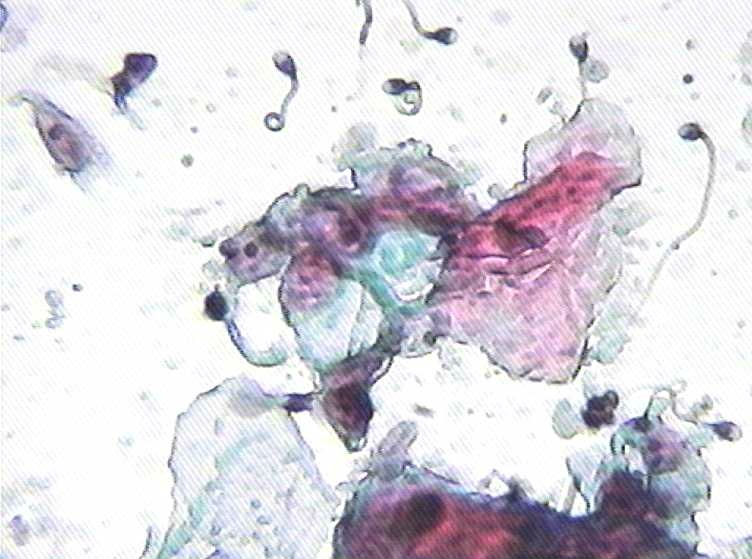

大家再看看这个病人是不是有UID细胞和其它一些异常细胞?

• 大家再看看这个病人是不是有UID细胞和其它一些异常细胞?图1

UID和ASCUS?